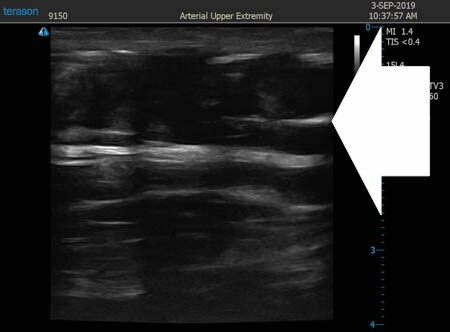

いつものように3Dタッチビュー(超音波)で

皮下脂肪層を評価してみましょう。

上腹部